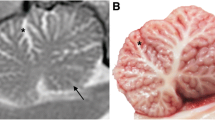

The overall size and volume ratios of ITPR1 mutant IS cerebella as well as the lobule and folia formation, the diameters of the fissures and sulci and the area of the subarachnoid space were within a normal range. Cerebellocortical layers were sharply delineated, the Purkinje cells (PC) were correctly placed and the granule cell layer presented with normal density and glomerula formation. Mild variations of the PC density (Fig. 5a) corresponded to the sublobular segmental pattern seen in age-matched control IS. In affected IS, the molecular layer exhibited some focal stellate cell hypercellularity (Fig. 5a). Dendritic and somatic changes of PC morphology were not evident. Fluorojade C accumulation was not seen in cerebellar neurons. On HE, peri-PC basket cell plexuses (BCP) appeared prominent (Fig. 5b). They stained physiologically with synaptophysin (Fig. 5c). Synaptophysin-positive halo-like structures, such as seen in human SCA-31 (Yoshida et al. 2014) were excluded. Upon Bielschowsky´s stain, BCP were sorted to type 0 to 2 at variable frequencies (Erickson-Davis et al. 2010) as they were in age-matched control dogs. Very occasionally (<1 BCP per lobule), empty baskets were detected (Fig. 5e). Even in morphologically inconspicuous PC, calbindin-D-28 k expression was inconstant and failed to highlight the dendritic morphology and orientation due to weak immunopositivity (Fig. 6b). Only a minority of PC (10–15 %) expressed ITPR1 strongly, with additional discrepancies regarding perikaryal versus dendritic staining. In control dogs, 100 % of Purkinje cells show strong ITPR1 expression throughout all lobules. Areas of ITPR1 expression in cases, however, allowed for identification of a distortion of the of monoplanar orientation of the dendritic trees. Instead of the two-dimensional arborisation in sagittal plane, the dendrites, now birch-broom-like, extended into the molecular layer towards the pial membrane. Thereby, secondary and tertiary dendrites and spiny branchlets left the stem at a moderately steep angle (Fig. 6d). Both reduced ITPR1 expression and the defective planar orientation of immunopositive cells involved all lobules and functional subfields of the affected cerebella with a mild emphasis on the spinocerebellar parts of the vermis. This notably co-localised with a moderately increased GFAP immunopositivity of Bergmann glia processes in the outer molecular layer. Bergmann´s astrocytosis was not evident on HE nor GFAP stained slides. MAP2 immunohistochemstry revealed a normal functional integration of stellate cells, basket cells, Golgi cells and granular cells. The overall histological appearance of the large afferent/efferent fibre tracks, cerebellar roof and feedback nuclei was normal. Only the density of ITPR1 positive presynapses appeared reduced in the cerebellar roof nuclei and vestibular nuclei.

Cerebellar cortex in ITPR1 mutant IS (a–c, e) versus controls (d). Cortical layering and Purkinje cell (PC) density (a black arrows) are within a normal range. The molecular layer (ML) shows occasional foci of mildly increased stellate cell density (a blue line). Dendritic and somatic PC changes are not evident on HE slides (a, b). Instead, the baskets (B) appear slightly prominent (b) on HE. The basket cell plexus morphology, on the other hand, is normal on synaptophysin (Syn c) immunohistochemistry and on Bielschowsky´s stain (Biel e). Very rarely, empty baskets are seen in the vermis (e arrowhead). GC granule cell, G synaptic glomerulus (Color figure online)

Dendritic morphology and expression of calbindin-D-28k and ITPR1 in SCA-affected IS (b, d) as compared to controls (a, c). On calbindin-D-28 k immunohistochemistry (b), ITPR1 mutant IS shows variable and inconstant antigen expression with scattered immunonegative PC somata (arrowhead) as well as with poorly stained PC dendrites (black arrows). A majority of about 90 % of PC stains negative or weakly positive for ITPR1 (d arrowhead). Stronger ITPR1 expression highlights the loss of planar orientation and dysmorphology of the PC dendritic tree (d DD). PD planar dendritic tree, DD dysmorphic dendritic tree, ML molecular layer